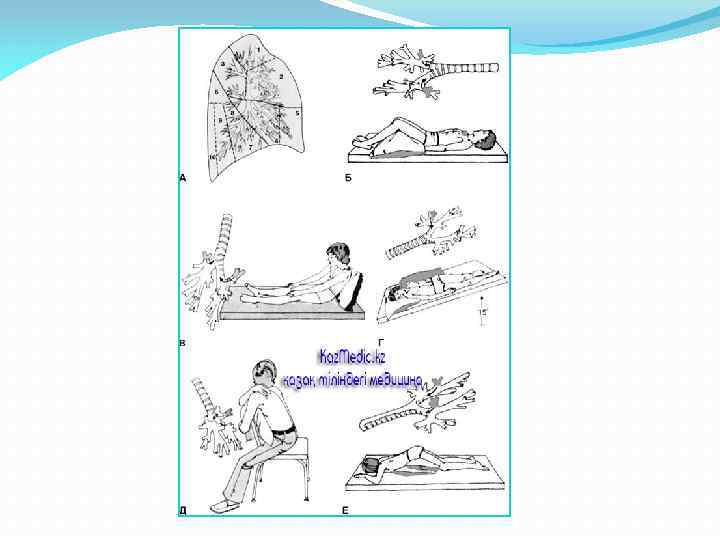

Өкпенің жедел іріңді абцессінің емі: Консервативті емі: Кең спектрлі антибиотиктерді көктамырға енгізу. Иммунотерапия: ронколейкин, интерлейкин-2, иммунофан, пентоглобин. Антистафилоккокты плазма. Консервативты терапия төсектік режим, науқасқа дренаждық қалып жасау ( күніне 10 -30 минут қақырық шығуы үшін) Антибактериалды терапия Аутогемотрансфузия Бронхоскопия (бронхоальвеолярлы лаваж) Хирургиялық ем Постуральды дренаж – денені көп мөлшерде какырык бөлінетіндей етіп орналастыру. Диаметрі 6 см-ден үлкен абцесс кезінде хирургиялық араласусыз консервативті ем тиімсіз.